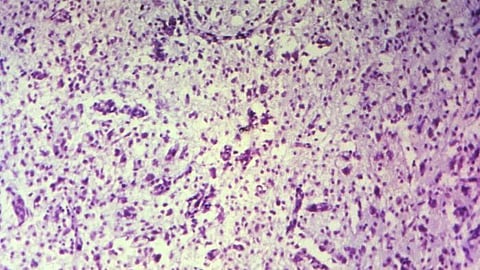

For the study, the researchers looked specifically at the dorsolateral prefrontal cortex (dlPFC), a brain region that is unique to primates and essential for higher-order cognition. Using a single cell RNA-sequencing technique, they profiled expression levels of genes in hundreds of thousands of cells collected from the dlPFC of adult humans, chimpanzees, macaque, and marmoset monkeys.

To answer this, the researchers first asked whether there are there any cell types uniquely present in humans or other analyzed non-human primate species. After grouping cells with similar expression profiles they revealed 109 shared primate cell types but also five that were not common to all species. These included a type of microglia, or brain-specific immune cell, that was present only in humans and a second type shared by only humans and chimpanzees.

The human-specific microglia type exists throughout development and adulthood, the researchers found, suggesting the cells play a role in maintenance of the brain upkeep rather than combatting disease.